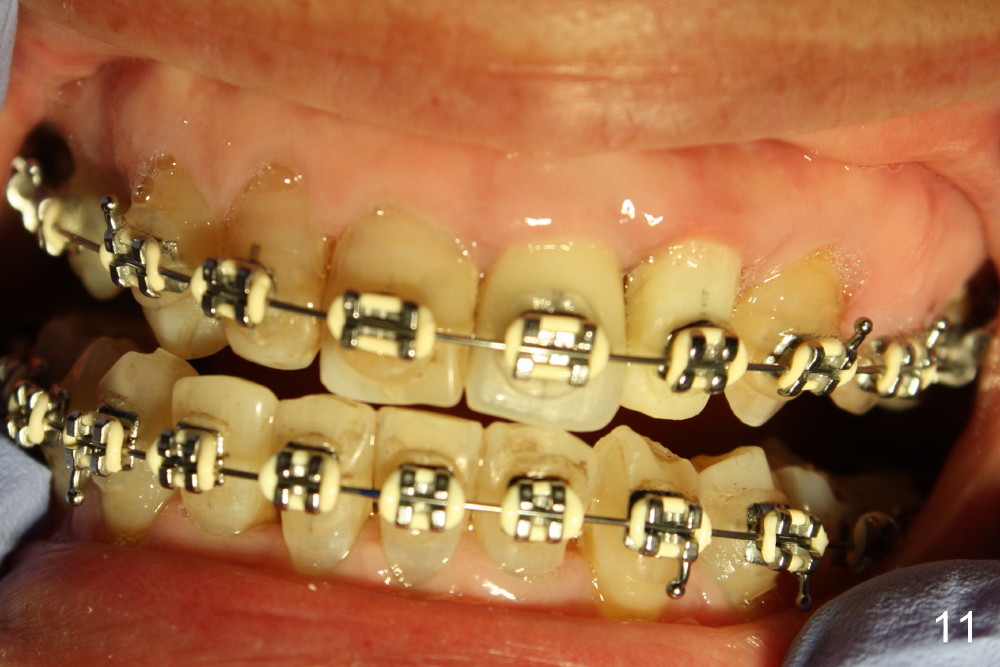

A prominent feature of implant failure in this case is pain. The patient feels that the pain is from the base of the nose. PA taken 3 days postop shows that the implant is inferior to the nasal floor (Fig.2 red ^). Clinically, the buccal gingiva continues to be erythematous 10 days postop (Fig.1). The pain is so unbearable that the implant (3.8x14 mm) is removed 10 days post placement. After repeated debridement, a 4.1 mm tap (Fig.3 T) is manually inserted with torque. A 4.1x14 mm submerged implant is placed with insertion torque < 30 Ncm, but it is placed subcrestally (Fig.4 <--). This time an immediate provisional is not provided. The flap is sutured. The pain disappears immediately. No infection is found 7 days postop (Fig.5). However, an asymptomatic vesicle is noted at the crest 3 weeks postop (Fig.6). The gingiva looks normal 2 and 3 months postop (Fig.7,8). The coronal gap dissolves 3 months postop (Fig.9 >, as compared to Fig.4), suggesting osteointegration. The implant is uncovered 4 months postop (Fig.10). Bracket is placed 5 months postop (Fig.10'). One month later, the left central incisor improves in position coronocervically (Fig.11), but the overjet needs correction by distalization of the upper anterior teeth. The implant at the site of #10 may be used as an anchorage.